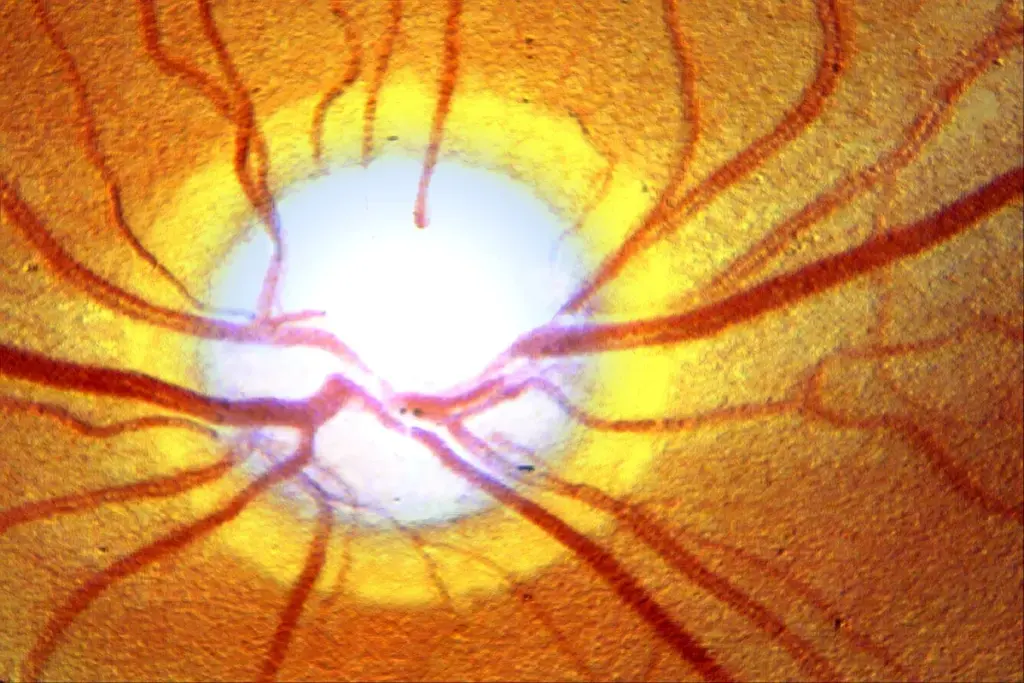

Structural Vulnerabilities of the Optic Nerve Head

The shape of the optic nerve head can also affect NTG. Structural vulnerabilities, like a thin or damaged optic nerve head, can make people more prone to glaucoma damage. Even at normal eye pressures.

Knowing about these structural issues is key to diagnosing and treating NTG. Advanced imaging can help spot these problems. This allows for more focused treatment plans.